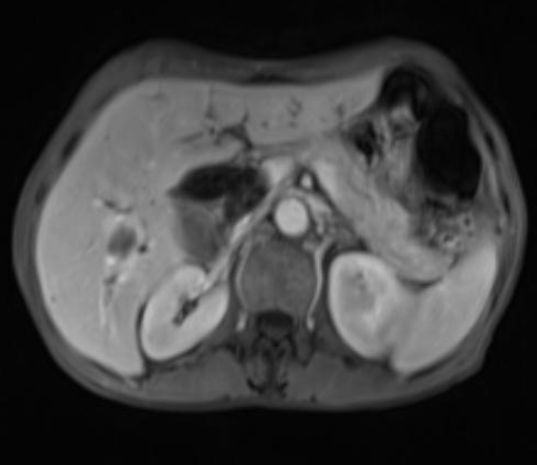

今天坐診,診室里來了一位患者,經(jīng)過了解得知患者姓張。張先生講述到,最近一個月左右他總是覺得肚子疼,晚上格外明顯,彎腰或者蹲著的時候疼得更嚴重了。于是我觀察張先生,發(fā)現(xiàn)他體型偏瘦,面色不好,偏黃。張先生補充道,他最近胃口不好,吃得很少,瘦了好多斤,以前比現(xiàn)在胖多了。于是我讓他躺到檢查床上,進行腹部檢查,發(fā)現(xiàn)張先生疼痛部位偏于上腹部,并且在偏右側(cè)觸診時還可以摸到一個堅硬、固定的腫塊。隨后我為張先生進行腹部的MRI檢查,檢查結(jié)果顯示胰腺部位有一腫塊,腫塊呈稍長T1、稍長T2信號影,動脈期、門靜脈期增強圖像顯示腫塊強化程度低。根據(jù)臨床表現(xiàn)和MRI檢查,遂懷疑為胰腺癌。

(MRI:腫塊呈稍長T1、稍長T2信號影,動脈期、門靜脈期增強圖像顯示腫塊強化程度低。)

手術(shù)行胰頭十二指腸切除術(shù)后,癌灶切除。術(shù)后李先生一般狀況良好、精神可、沒有明顯不良反應(yīng),手術(shù)創(chuàng)口沒有出現(xiàn)破潰、異常滲血、異常滲液的情況。輔助化療一月后,李先生腹部疼痛的癥狀得到控制,配合胰制酶劑消化不良的表現(xiàn)得到改善,體重稍有增加,面色逐漸好轉(zhuǎn)。復(fù)查腹部MRI檢查,暫時沒有發(fā)現(xiàn)轉(zhuǎn)移和復(fù)發(fā)的情況?,F(xiàn)隨訪一年,李先生依舊勇敢堅強的對抗病魔,讓人欽佩。